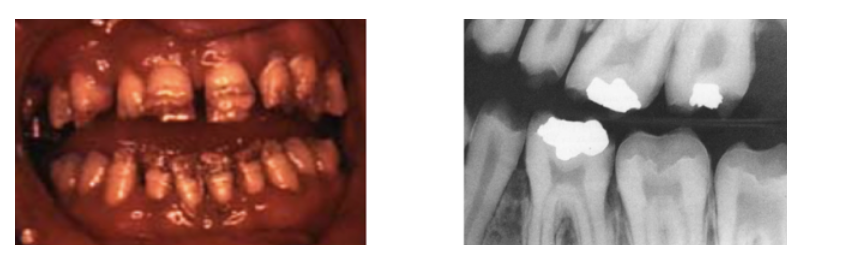

Amelogenesis Imperfecta

A

Failure in Bell Stage

Autosomal dominant, recessive, or x-linked

* intrinsic alteration of enamel

* affects all teeth (primary & permanent)

* thin to no enamel, dentin and pulp not afffected

* tx: Full coverage crowns for esthetics